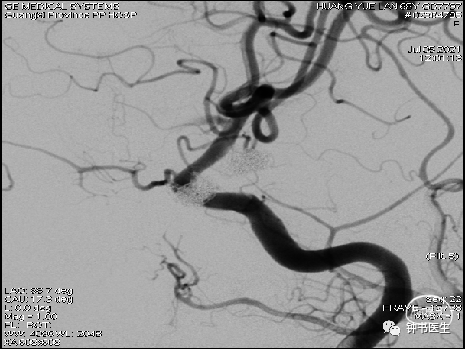

2021-07-05 DSA